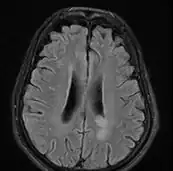

text: From left to right: Cryptococcosis lung, cryptococcosis brain | |

Brain

Cryptococcal meningitis (infection of the meninges, the tissue covering the brain) is believed to result from dissemination of the fungus from either an observed or unappreciated pulmonary infection. Often there is also silent dissemination throughout the brain when meningitis is present. Cryptococcus gattii causes infections in immunocompetent people (fully functioning immune system), but C. neoformans v. grubii, and v. neoformans usually only cause clinically evident infections in persons with some form of defect in their immune systems (immunocompromised persons). People with defects in their cell-mediated immunity, for example, people with AIDS, are especially susceptible to disseminated cryptococcosis. Cryptococcosis is often fatal, even if treated.[19]

Though the rate of infection is clearly higher with immunocompromised individuals, some studies suggest a higher mortality rate in patients with non-HIV cryptococcal meningitis secondary to the role of T-cell mediated reaction and injury.[20] CD4+ T cells have proven roles in the defense against Cryptococcus, but it can also contribute to clinical deterioration due its inflammatory response.[21]

CT scan lungs: mass in right upper lobe MRI brain: cryptococcus

The immune reconstitution inflammatory syndrome (IRIS) has been described in those with normal immune function with meningitis caused by C. gattii and C. grubii. Several weeks or even months into appropriate treatment, there can be deterioration with worsening meningitis symptoms and progression or development of new neurological symptoms. IRIS is however much more common in those with poor immune function (≈25% vs. ≈8%).Magnetic resonance imaging shows increase in the size of brain lesions, and CSF abnormalities (white cell count, protein, glucose) increase. Radiographic appearance of cryptococcal IRIS brain lesions can mimic that of toxoplasmosis with ring enhancing lesions on head computed tomography (CT). CSF culture is sterile, and there is no increase in CSF cryptococcal antigen titre.